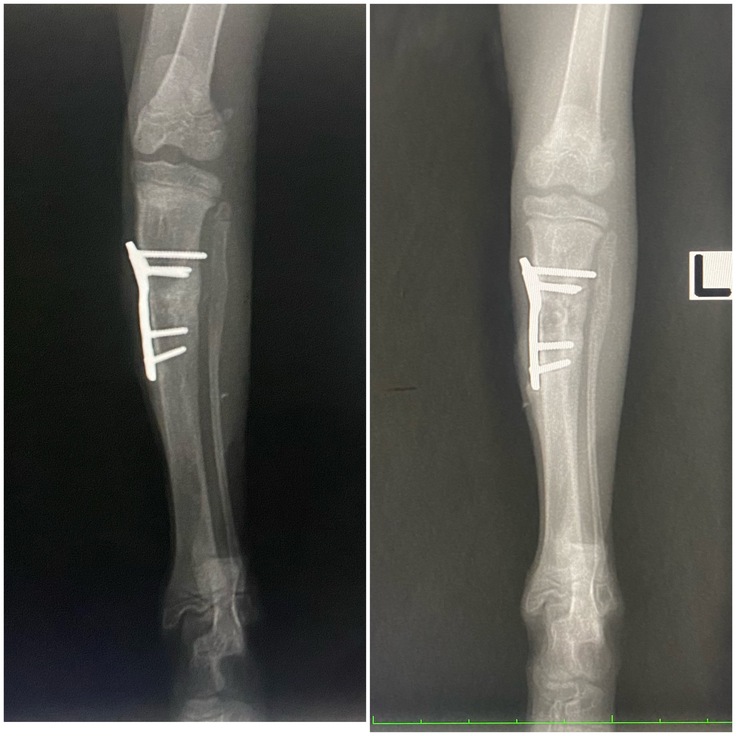

右前足

↑今日 前回8/8↓

前回はまだ亀裂がうっすら残っていましたが、隙間なくしっかりとしっかりと癒合しました🎉